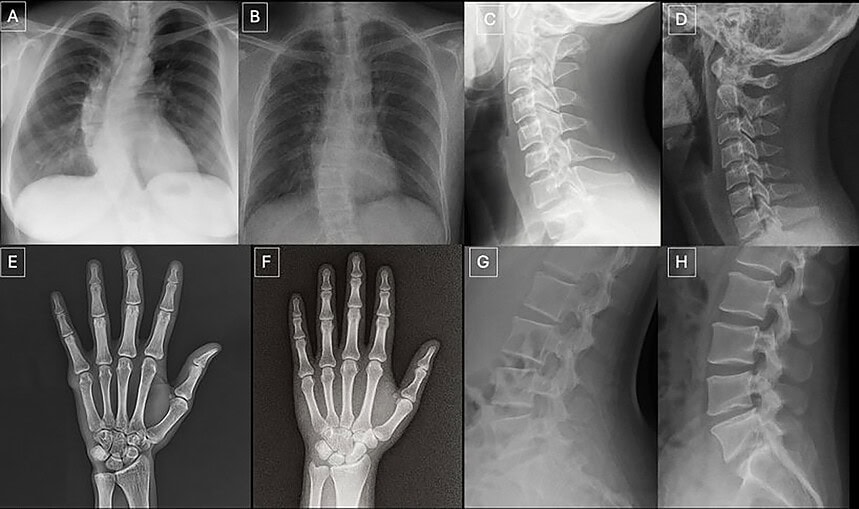

Yapay zekâ tartışması yeni bir eşiğe daha geldi. Bu kez mesele sadece fotoğraf, video ya da ses üretmesi değil. Son araştırmalara göre yapay zekâ, gerçeğine çok benzeyen sahte röntgen görüntüleri de üretebiliyor. Dahası, bu görüntüler bazı radyologları ve bazı yapay zekâ sistemlerini bile yanıltabiliyor.

Araştırmada 12 farklı merkezden, 6 ülkeden 17 radyolog yer aldı. Toplam 264 röntgen görüntüsü incelendi. Bu görüntülerin yarısı gerçekti, yarısı ise yapay zekâ ile üretilmişti. Radyologlar ilk aşamada, görüntülerin sahte olabileceği özellikle söylenmeden değerlendirme yaptı. Sonuç çarpıcıydı: Sahte görüntüleri doğru ayırt etme oranı yalnızca yüzde 41’de kaldı. Katılımcılara görüntüler arasında yapay zekâ ile üretilmiş olanlar da bulunduğu söylendiğinde bu oran yüzde 75’e çıktı. Yani uzmanlar uyarıldığında daha başarılı oldu ama ilk bakışta sahte görüntüler ciddi biçimde kafa karıştırdı.

Üstelik sorun sadece insanlar değil. Reuters’ın aktardığına göre GPT-4o, GPT-5, Gemini 2.5 Pro ve Llama 4 Maverick gibi gelişmiş sistemler de sahte röntgenleri ayırt etmede değişen oranlarda zorlandı. Bazı modeller daha iyi sonuç verdi, bazıları daha düşük doğrulukta kaldı. Bu da yapay zekânın, başka yapay zekâları bile yanıltabilecek kadar ikna edici tıbbi görüntüler üretebildiğini gösteriyor.

Buradaki asıl tehlike, kötüye kullanılma ihtimali. Araştırmacılar bu tür görüntülerin dolandırıcılık, yanlış teşhis, sahte hasta kaydı, sigorta suistimali ya da sağlık verisinin manipülasyonu gibi alanlarda kullanılabileceği uyarısında bulunuyor. Radyoloji gibi güvenin temel olduğu bir alanda, görüntünün gerçek olup olmadığından emin olamamak çok daha büyük bir sorunun kapısını açıyor. Bu yüzden çalışma aynı zamanda, sağlık sisteminde güvenlik ve doğrulama sorunu olarak görünüyor.

Araştırmanın bir başka dikkat çekici bulgusu da şu: Uzmanlık süresi her zaman koruma sağlamıyor. ScienceDaily’nin aktardığına göre radyologların yıllar içindeki deneyimi ile sahte görüntüleri yakalama başarısı arasında güçlü bir ilişki bulunmadı. Buna karşılık kas-iskelet alanında çalışan bazı radyologların daha iyi performans gösterdiği belirtildi. Yani tecrübeli bir doktorun, sahte röntgeni hemen anlayabileceği gibi bir bilgi çok da kanıtlanabilir bir gerçek değil.

Peki çözüm ne olabilir? Uzmanlar, tıbbi görüntülere görünmez filigranlar eklenmesi, cihazdan çıktığı anda kriptografik imza oluşturulması ve görüntülerin kaynağının teknik olarak doğrulanması gibi yöntemler öneriyor. Bir başka deyişle, yapay zekâ güçlendikçe sadece teşhis araçlarını değil, doğrulama mekanizmalarını da güçlendirmek gerekecek.

Kısacası yapay zekâ artık sadece sanatçıyı, yazarı ya da tasarımcıyı tedirgin etmiyor. Şimdi sağlık sisteminin en hassas alanlarından birine de dokunuyor. Röntgen gibi en temel görüntüleme araçlarında bile gerçeğe çok yakın sahteler üretilebiliyorsa, önümüzdeki dönemde asıl soru şu olacak: Gördüğümüz şey gerçekten bir hastaya mı ait, yoksa yapay zeka tarafından çok iyi üretilmiş sahte bir görüntü mü?